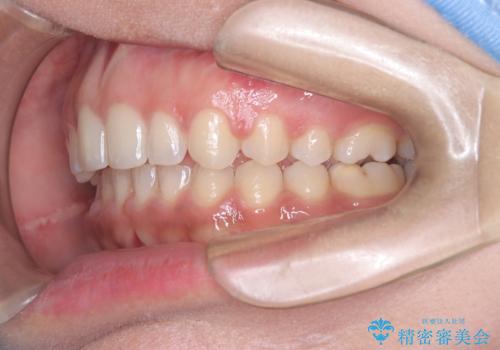

上顎前突を非抜歯で改善

本症例では、非抜歯での治療を選択したため、スペースを確保するためにIPR(歯間削合)を行い、歯列を整えました。オーバージェット(上の前歯と下の前歯の水平的なズレ)は残る結果となりましたが、見た目や機能の改善を重視し、患者様と治療計画を共有しながら進めました。治療中は、歯列全体のバランスと噛み合わせを考慮しつつ、矯正装置の適切な使用を徹底しました。当初の計画通りに治療を完了し、患者様にも満足していただけました。